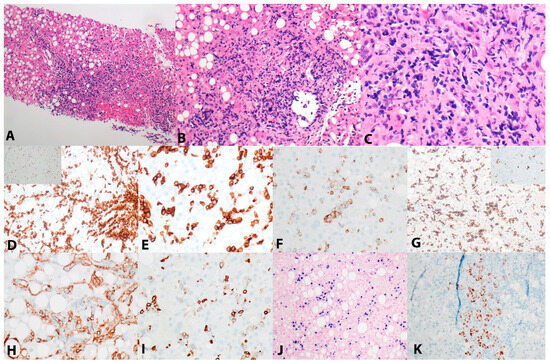

2. Case Presentation

3. Results